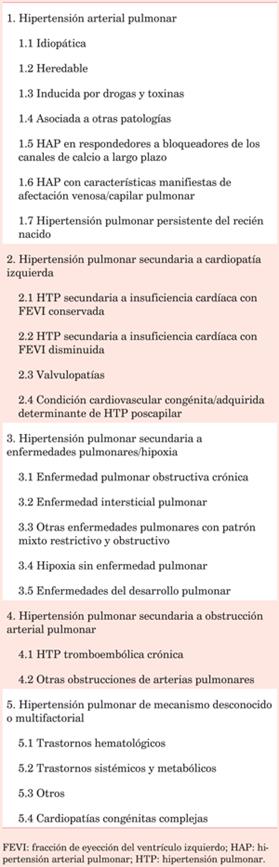

En el 6º Simposio Mundial de HTP5 se ha actualizado la clasificación clínica (tabla 1), agrupando los procesos y las enfermedades que la originan en cinco grupos que se diferencian por sus mecanismos fisiopatológicos, presentación clínica y opciones terapéuticas.

En la (tabla 2) se reúnen los diferentes tipos hemodinámicos junto a la correspondiente definición clínica. La enfermedad HTP inducida por ejercicio, no ha sido definida2. Las últimas guías recomiendan no utilizar este término debido a la falta de evidencia que demuestre a partir de qué valor de PAPm durante el ejercicio sobrevienen implicancias pronósticas6.